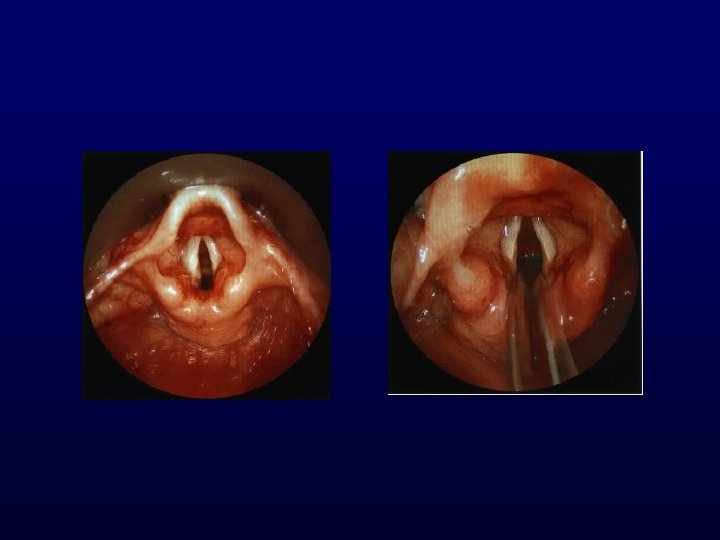

LARINGE Exploración Palpación Movilidad Fonación Ventilación Laringoscopía indirecta por espejo

LARINGE Exploración Laringoscopía indirecta por espejo

Anterior Derecho Izquierdo Posterior